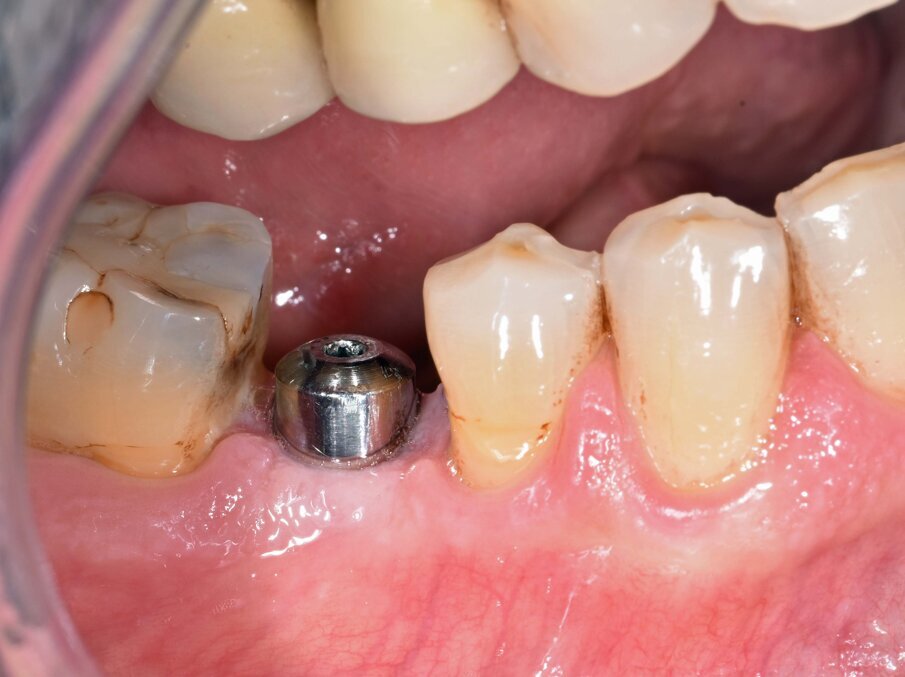

L’estrusione completa del frammento ha richiesto un tempo di 6 mesi, durante i quali è stata modificata più volte l’inclinazione della molla per evitare che il movimento diventasse ortogonale al segmento e mantenere la traiettoria prevista. Così facendo, è stato possibile rigenerare naturalmente l’intero alveolo e inserire, dopo 3 mesi di ulteriore maturazione del tessuto, in un contesto osseo ideale e perfettamente rigenerato un impianto Syra (Sweden & Martina) di diametro 4.25 mm e lungo 11 mm.

Dopo 3 mesi dall’inserimento implantare è stato possibile prendere un’impronta e di precisione e realizzare una corona singola avvitata.